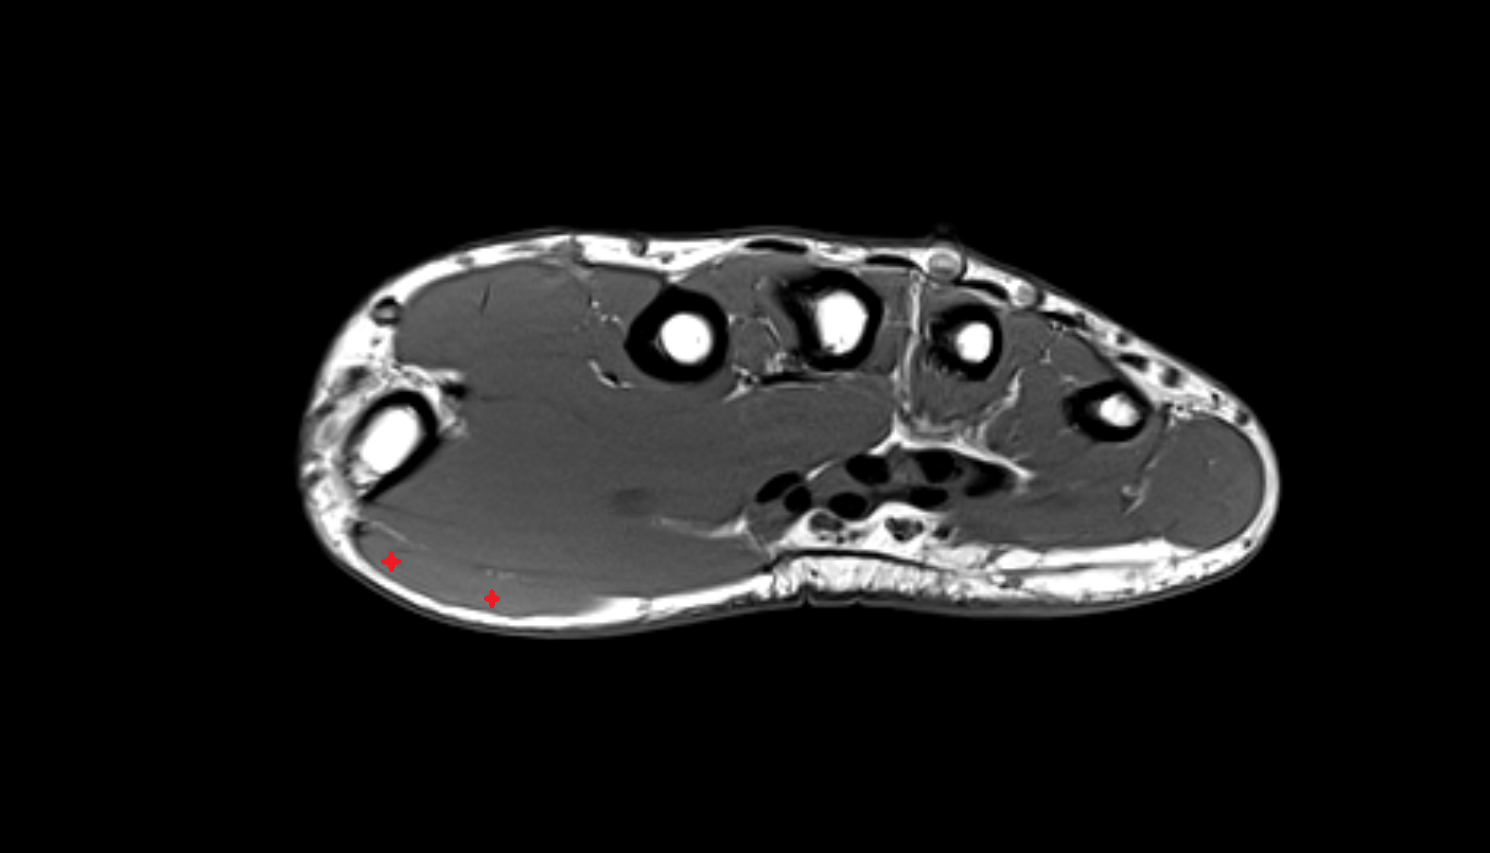

- Plantar aponeurosis